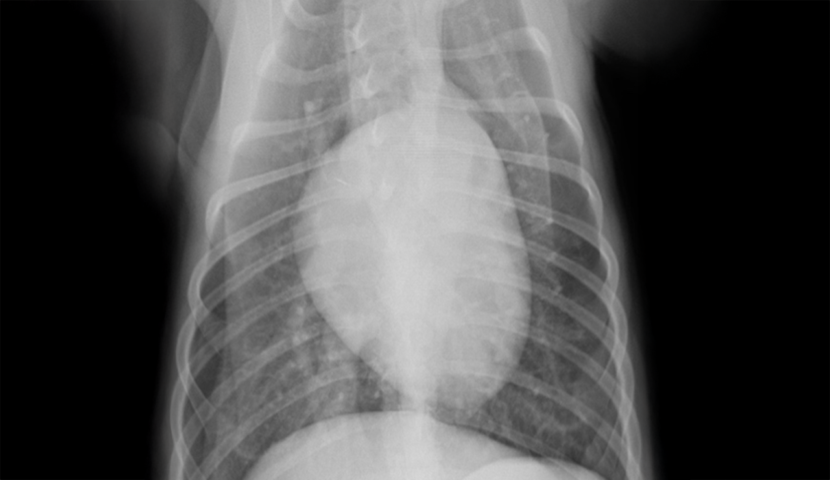

胸部のレントゲン撮影にて肺野全体の不透過性亢進(白く見える部分)が認められた。

| 誤嚥性肺炎とは、唾液や食べ物、胃液、吐物などの異物を吸引してしまうことで生じる肺炎です。加齢などにより気道反射が低下している動物や短頭種(パグやブルドッグなど)で起こりやすいと言われています。 本症例は上記の条件に当てはまりませんが、スポンジをかじる中で細かい粒子を吸い込んでしまった可能性があります。 幸いにも、本症例は抗生物質の投与により2週間ほどでレントゲン画像所見は消失し治療終了となりましたが、場合により致命的な状態まで悪化してしまうこともあります。早期発見・治療が重要です。 |